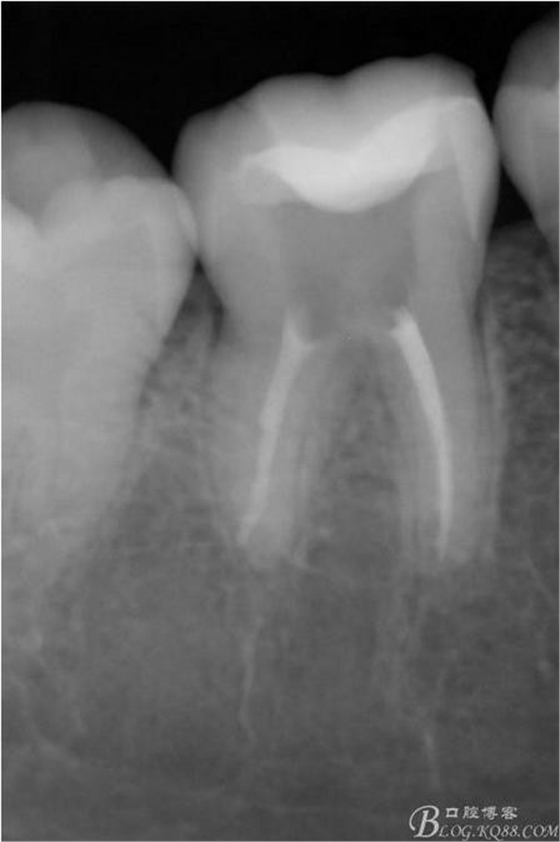

X線:雙側(cè)下6 齲壞已接近髓腔

粘接后X線片